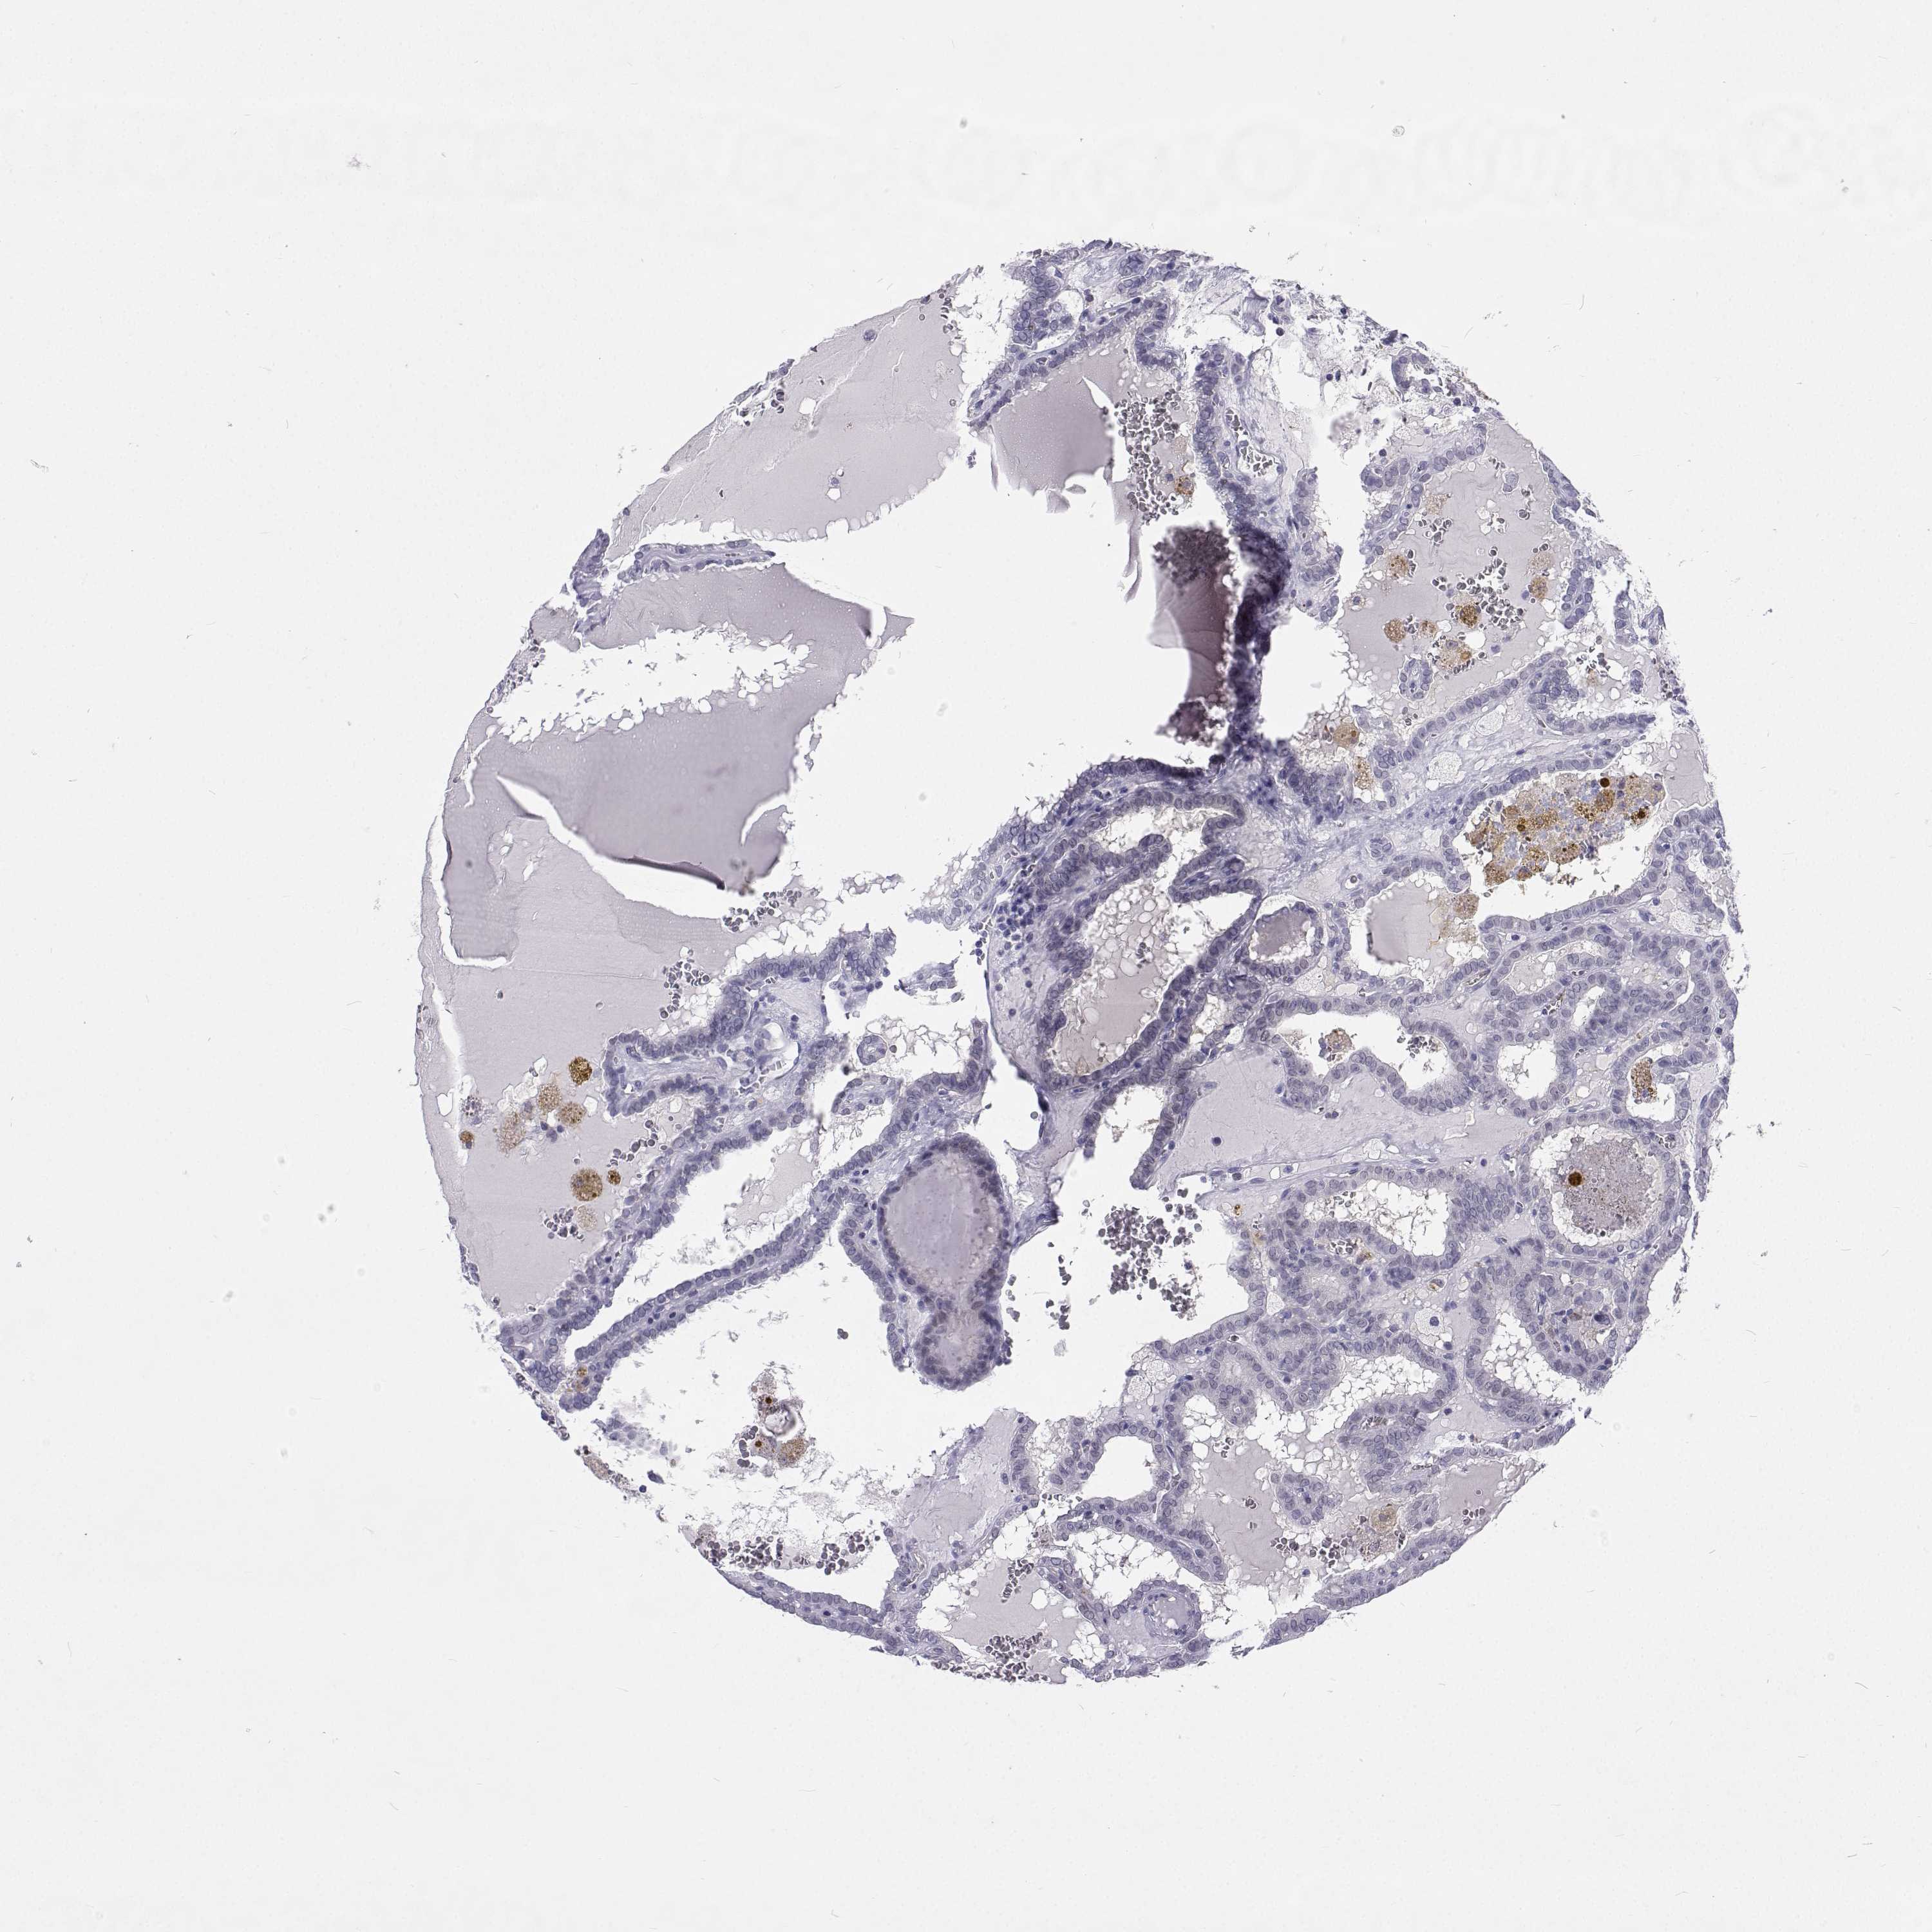

THYROID CANCER - Protein expressioni

A mouse-over function shows sample information and annotation data. Click on an image to view it in a full screen mode. Samples can be filtered based on level of antibody staining by selecting one or several of the following categories: high, medium, low and not detected. The assay and annotation is described here.

Note that samples used for immunohistochemistry by the Human Protein Atlas do not correspond to samples in the TCGA dataset.

Antibody stainingi

Antibody staining in the annotated cell types in the current human tissue is reported as not detected, low, medium, or high, based on conventional immunohistochemistry profiling in selected tissues. This score is based on the combination of the staining intensity and fraction of stained cells.

Each image is clickable and will lead to virtual microscopy that enables deeper exploration of all samples and also displays staining intensity scores, fraction scores and subcellular localization as well as patient and tissue information for each sample.

Papillary adenocarcinoma, NOS

Follicular adenoma carcinoma, NOS